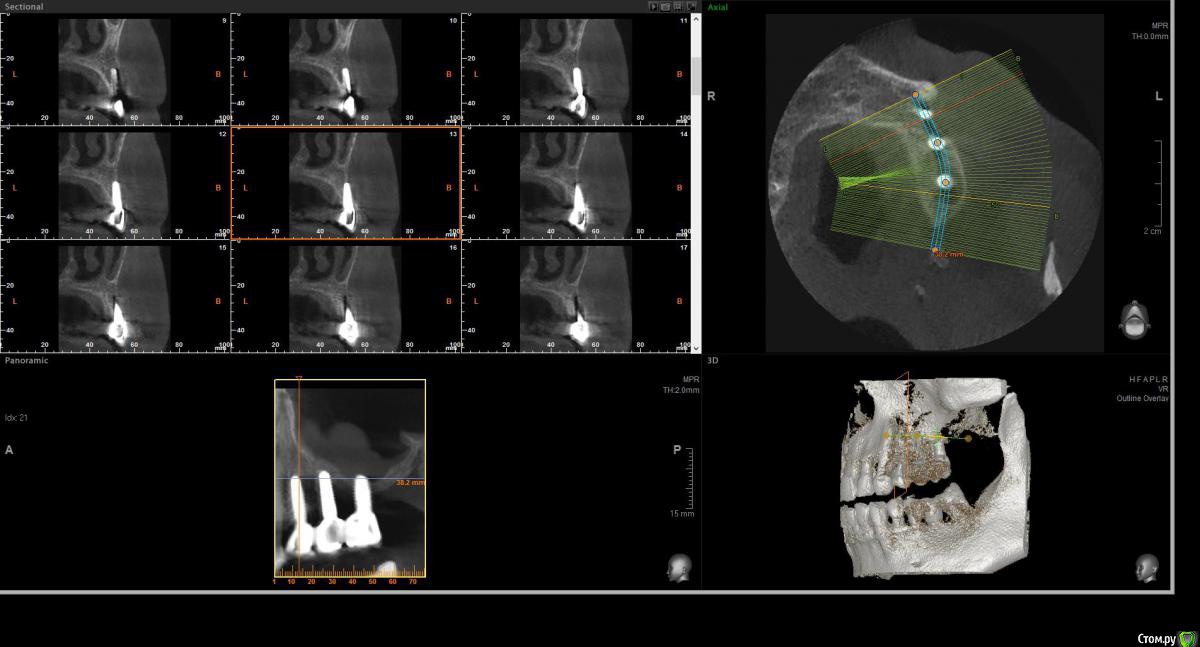

wladdX Опубликовано 20 марта, 2017 Поделиться Опубликовано 20 марта, 2017 (изменено) Несколько скриншотов на скорую руку и снимок из архива, видимо внутриротовая Rg Изменено 20 марта, 2017 пользователем wladdX Ссылка на комментарий

filvik Опубликовано 22 марта, 2017 Автор Поделиться Опубликовано 22 марта, 2017 (изменено) wladdX Спасибо, не знал какие слои выделить.За три года толщина кости уменьшилась где-то на три милиметра.Зубки в коронке стали выше на те-же три милиметра. Изменено 22 марта, 2017 пользователем filvik Ссылка на комментарий

filvik Опубликовано 24 марта, 2017 Автор Поделиться Опубликовано 24 марта, 2017 Как-то, так.К 3-D КТ приложен рентгеновский снимок то, что было в конце в 2013 года, по ниткам резьбыхорошо видна толщина кости в которой сидит дальний имплант (при длине импланта 9 мм.), на КТ 2017 годавидно что с дальней стороны последнего зуба осталось 1,8 милиметра кости.Коронки ставить 1+2 или на каждый отдельно, да и задний имплант похоже держится на честном слове.Вопрос остался прежний что предпринять в данной ситуации? Ссылка на комментарий